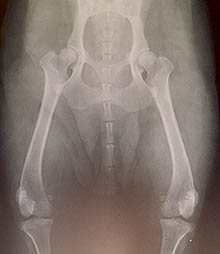

This is Jasmine, Ch. Sheeba Let's Dance . She was filmed at 3½ years old, and they look pretty good: her hips are rated "GOOD". Jasmine's OFA certification number is KCS-1662G42F-PI. Indicating that the dog has permanent identification (DNA profile, tattoo, or microchip), the OFA indicates that the dog IS identified - "PI" means "Permanent Identification".